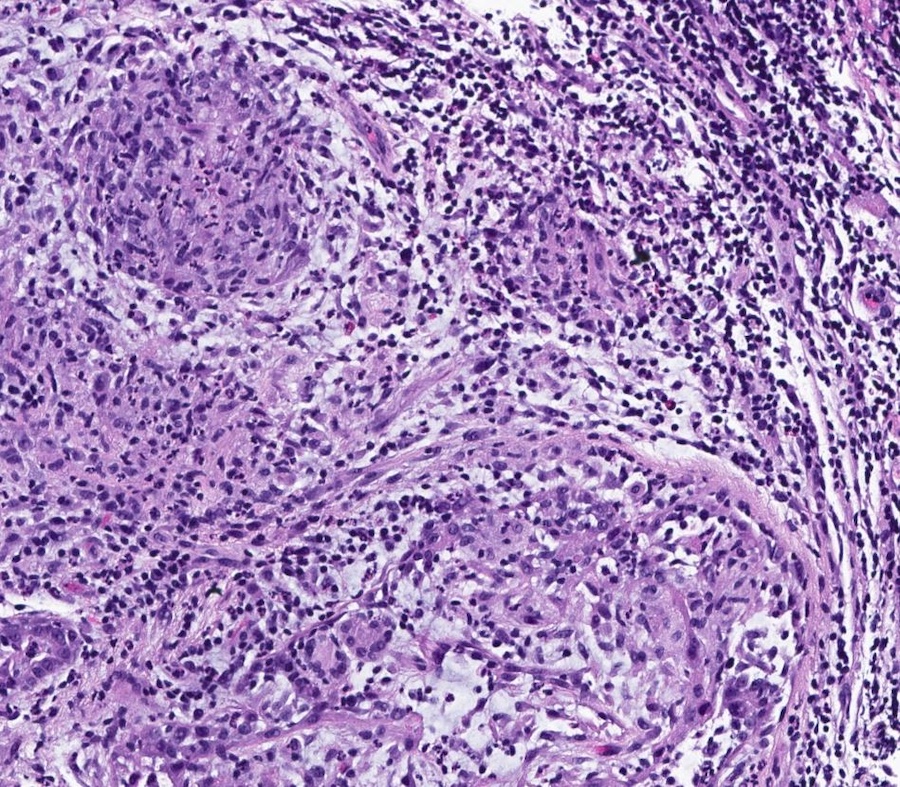

Microscopic (histologic) description

- Lobulocentric granulomatous inflammation (Pathology 2004;36:254)

- Granulomas often contain neutrophils

- Neutrophils can create microabscesses; overlapping features with cystic neutrophilic granulomatous mastitis

- Multinucleated giant cells, lymphocytes, plasma cells and eosinophils within and around lobules

- Extensive inflammation might obliterate lobulocentric distribution

- Caseous necrosis not present

- Schauman and asteroid bodies not common

Microscopic (histologic) images